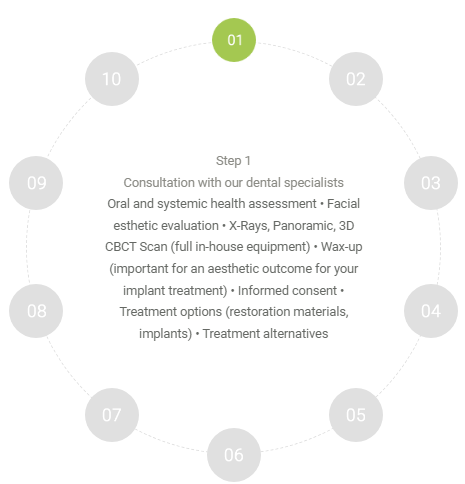

Treatment Process

Surgical phase step by step